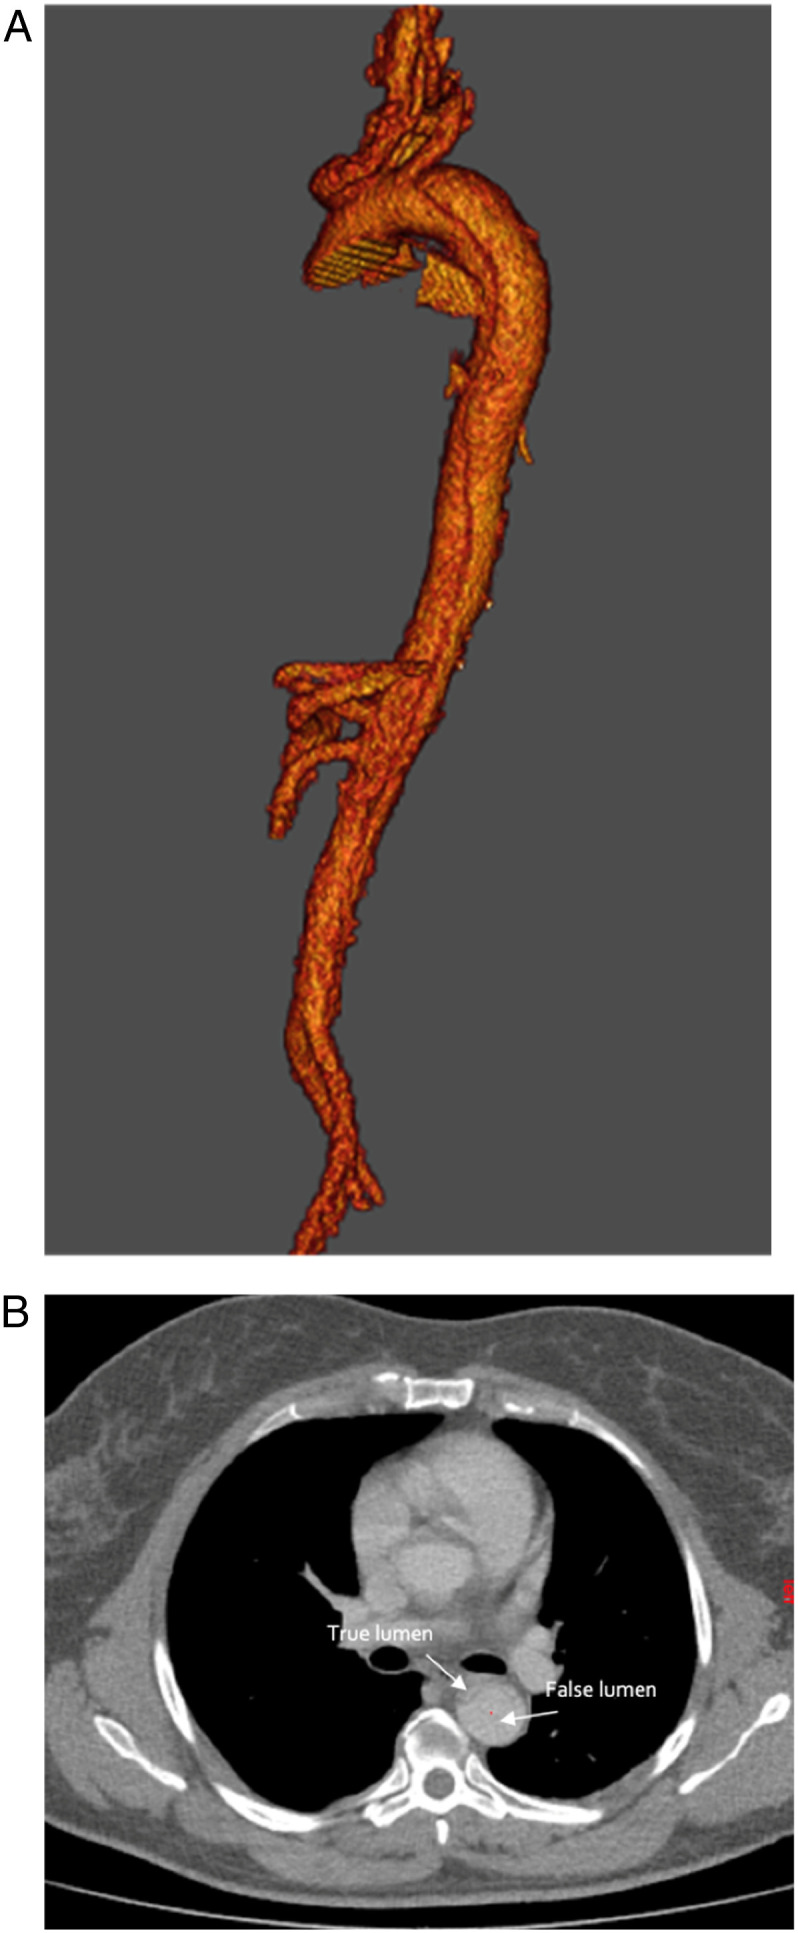

Case report: A 50-year-old female patient presented to the emergency department with an acute type B aortic dissection. Conservative medical treatment did control blood pressure but did not alleviate her dissection symptoms. She was treated endovascularly with multilayer stents extensively covering the whole dissected area. HThe aortic arch side branches, visceral arteries and renal arteries remained patent after treatment. The recovery was uneventful, and she was discharged the day after the intervention. At 6- and 12-month follow-up, the patient remained asymptomatic, the true lumen volume increased and all side branches remained patent.

Conclusion: We present a case of the use of a multilayer stent for acute type B aortic dissection. This technique allows to treat the whole dissection with low risk of paraplegia or side branch occlusion. Long-term results of ongoing clinical studies should confirm the place of the multilayer stent as a treatment option for type B aortic dissection.